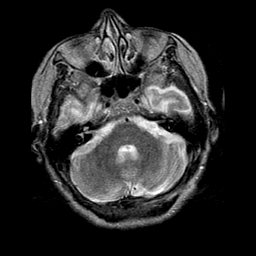

Pick's Disease, MR Study mr-t2 -- Slice #5

[Home][Help][Clinical] Slice 5